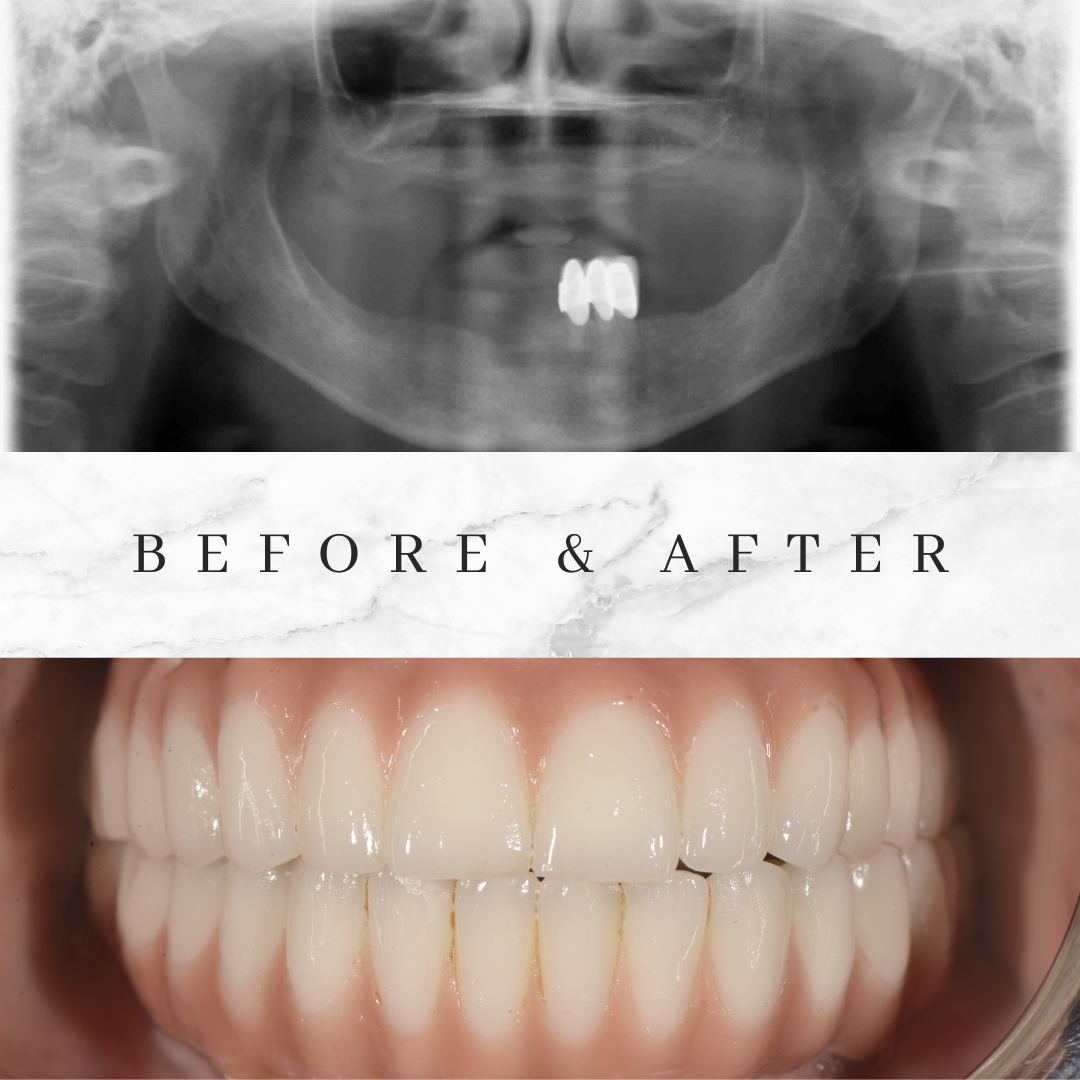

The implants you need will be placed in the upper and lower jaw. The Porcelain or Zirconia crowns will be made in the upper and lower jaw. You should come to istanbul 2 times for this treatment.At the first visit 2 days staying is enough for tooth extraction and placing the implants if you don’t need a temporary prosthesis.İf you need temporary prosthesis you can better stay 7 days in İstanbul.There is a waiting period of 6 weeks after implant treatment,Because the implants will fuse with the jawbone.At the second treatment after 6 weeks Porcelain or Zirconia crowns will be placed in the lower and upper jaw and you will get aesthetic look,healthy teeth and perfect smile.

Whenever you look at the mirror, if the image caused by the shape, color, and shortness of your teeth bothers you, the smile design can be the key to the change you want. With the smile design, not only your teeth, but also your gums, lips and face are evaluated as a whole. Parameters such as your facial features, lip structure, gum levels, gender, skin color and even your character are evaluated and a special treatment plan is prepared for you. With a correct planning, your smile can erase the years on your face, and Hollywood smile can be your signature.

We will discuss your desires and based on your digital panoramic x-ray. We can give you an approximate price offer as well as time needed for completion of the dental work.